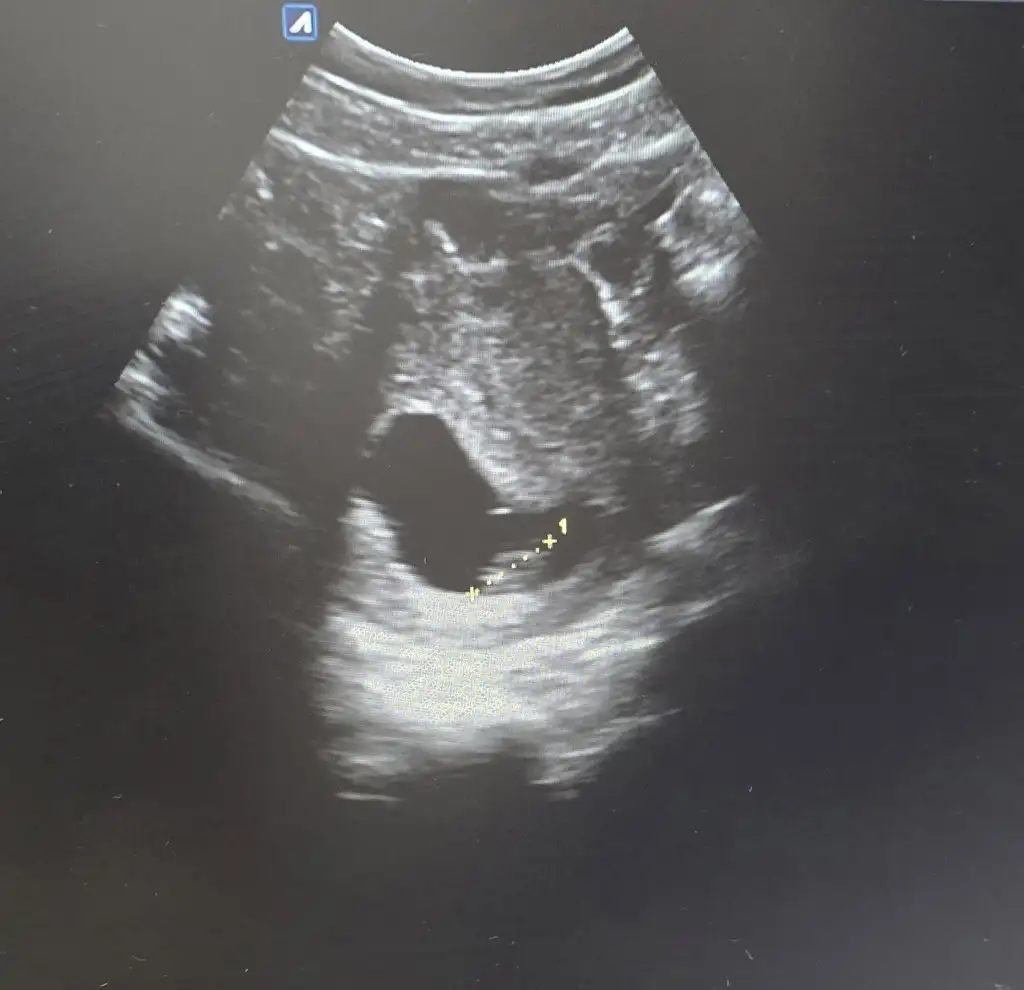

Merhaba benimkininde yorumlar mısınızHayırlısı canım. Inşallah erkektir. Sağlıkla kucağına al tatlım

Biri bana da bakabilir miii lütfenn ben hiç bisey anlamiyorummmRamzi teorisine göre ( bilimsel bir araştırma sonucuymuş ve %85 doğruluğu varmış). İlk 6-8 haftalık ultrason görüntüsüne göre bebeğin kesenin içersinde soldan ya da sağdan girişine göre cinsiyet tahmini yapılıyor. Bilimsel olunca tecrübeli annelerimiz yada anne adaylarımızdan yardım istiyoruz. Doğruluğu var mı öğrenmek adına :) Bizleri aydınlatırsanız çok seviniriz. bu teorieye göre;

Vajinal muayeneyle bakıldıysa eğer;

Sağdan girmiş gözüküyosa aslında solmuş ve ERKEK,

Soldan girmiş gözüküyosa aslında sağmış ve KIZ ,

Karından bakıldıysa eğer,

Soldan girmiş gözüküyosa gerçektede solmuş ve ERKEK,

Sağdan girmiş gözüküyosa gerçekte de sağmış ve KIZ,